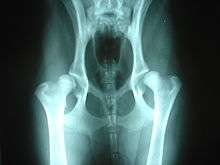

A number of conditions in dogs may be aggravated by or may show slow or no improvement as a result of weight bearing exercise. Among these are hip dysplasia and osteochondritis dissecans (OCD), conditions most common in medium to large purebred dogs, such as German Shepherds, Labradors or Golden Retrievers; chronic degenerative radiculomyelopathy (CDRM), a degenerative disease of the spinal cord which causes hind limb problems in German Shepherds; and luxating patella which is seen predominantly in small and toy breeds.